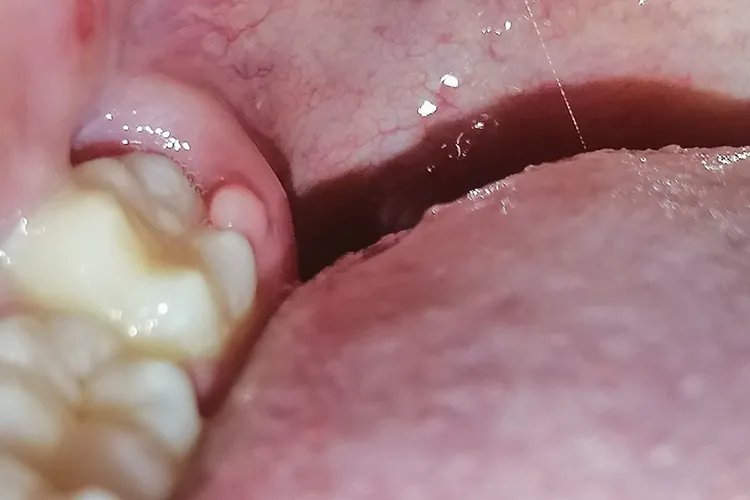

牙龈炎牙龈炎患者由于局部组织水肿,龈缘变厚,不再紧贴牙面,龈乳头变的圆钝肥大,有时可呈球状增生,甚至可覆盖部分牙面。少数患者的牙龈炎症严重时,可出现龈缘糜烂或有肉芽增生。